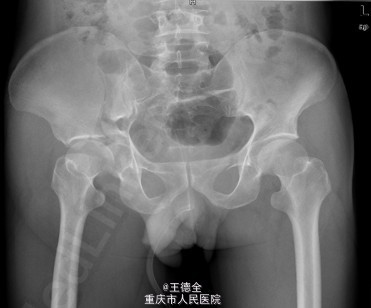

患者男性,51岁,因“高坠伤致左腰部及右髋部疼痛伴活动障碍3天”入院。急性痛苦面容,神志清楚,平车送入病房,右髋部软组织稍肿胀,局部皮肤完整,未见明显皮疹,挫擦伤及出血点.右股骨髁上骨牵引在位,左腰椎伴明显压痛,骨盆挤压实验阳性,可扪及骨擦音,骨擦感.双下肢感觉,活动,血循良好,足背动脉搏动好;右踝关节主动活动受限,被动活动正常。右侧各足趾背伸、跖屈活动正常,其余各关节活动正常。骨盆X线片示:右侧髂骨、髋臼、双侧耻骨上支、右侧耻骨下支多发骨折,左侧髂骨翼骨折,骨盆出入口右侧份形态失常。 初步诊断:右髋臼粉碎性骨折(Judet X 型) 诊疗计划:完善双下肢静脉彩超等检查;给予预防深静脉血栓、骨牵引治疗;给予止痛等对症支持治疗;密切观察病情变化,根据病情及时处理。